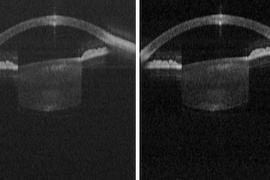

New VCSEL offers simpler, cheaper OCT

Medical University of Vienna believes inexpensive source could allow OCT imaging at home.